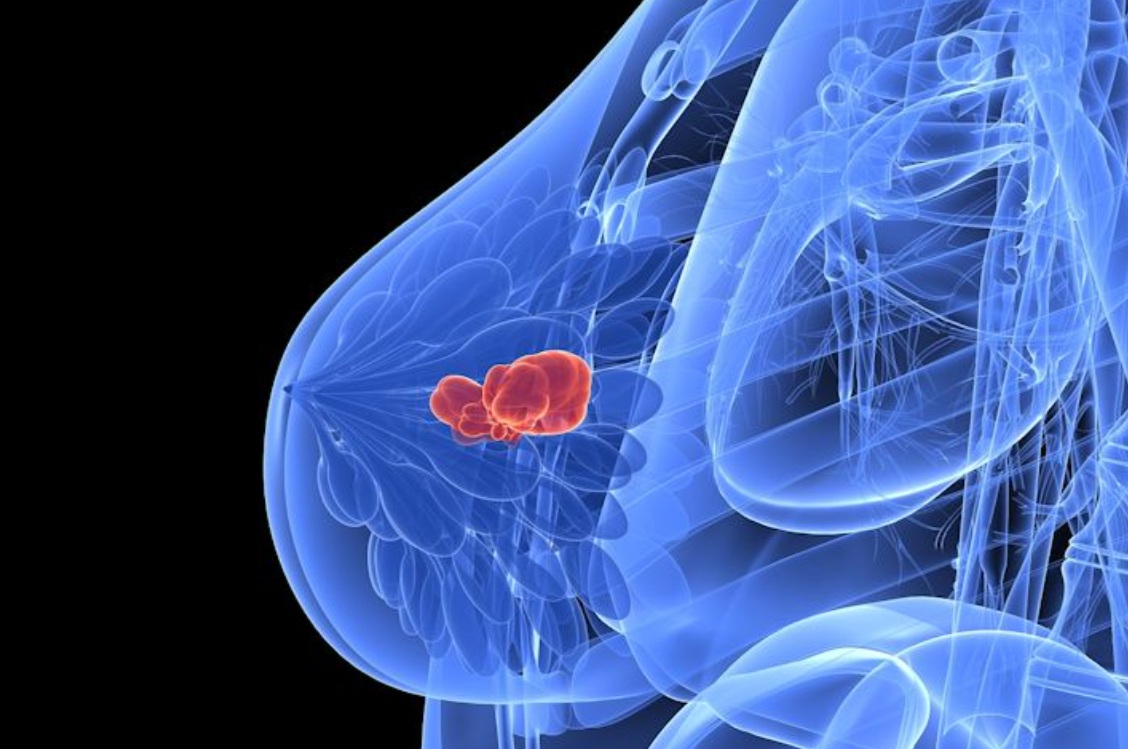

كشفت دراسة حديثة من مختبر "كولد سبرينغ هاربور" في نيويورك عن تطور واعد في علاج سرطان الثدي الثلاثي السلبي، وهو من أكثر أنواع السرطان شراسة وانتشاراً بين النساء الشابات.

ويؤكد الباحثون أن هذا الاكتشاف قد يفتح الباب أمام علاجات وقائية جديدة وفعالة لسرطان الثدي الثلاثي السلبي، مما يجعله إنجازاً علمياً مهماً في مواجهة هذا النوع العنيف من السرطان.